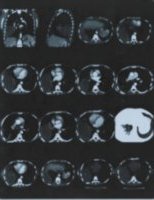

![]() Рис. 2 |

Так или иначе состояние улучшилось настолько, что у меня хватило физических сил наконец-то пройти полное медицинское обследование. Результаты были удручающими, первый же рентгеновский снимок (рис. 1) показал наличие опухоли в лёгком размером с грейпфрут, последующая компьютерная томография показало эту опухоль уже во всей красе (рис. 2). Помимо опухоли, на снимках видно, что заболеванием была полностью затронута печень, именно поэтому организм перестал принимать и перерабатывать пищу. Врачи в один голос требовали срочного оперативного вмешательства. Был поставлен предварительный диагноз – рак, для подтверждения, которого необходимо было провести биопсию, от которой я отказался. Кроме того, мой отказ был мотивирован еще и тем, что вопреки всем исследованиям, по личным ощущениям моё состояние с каждым днем становилось всё лучше.